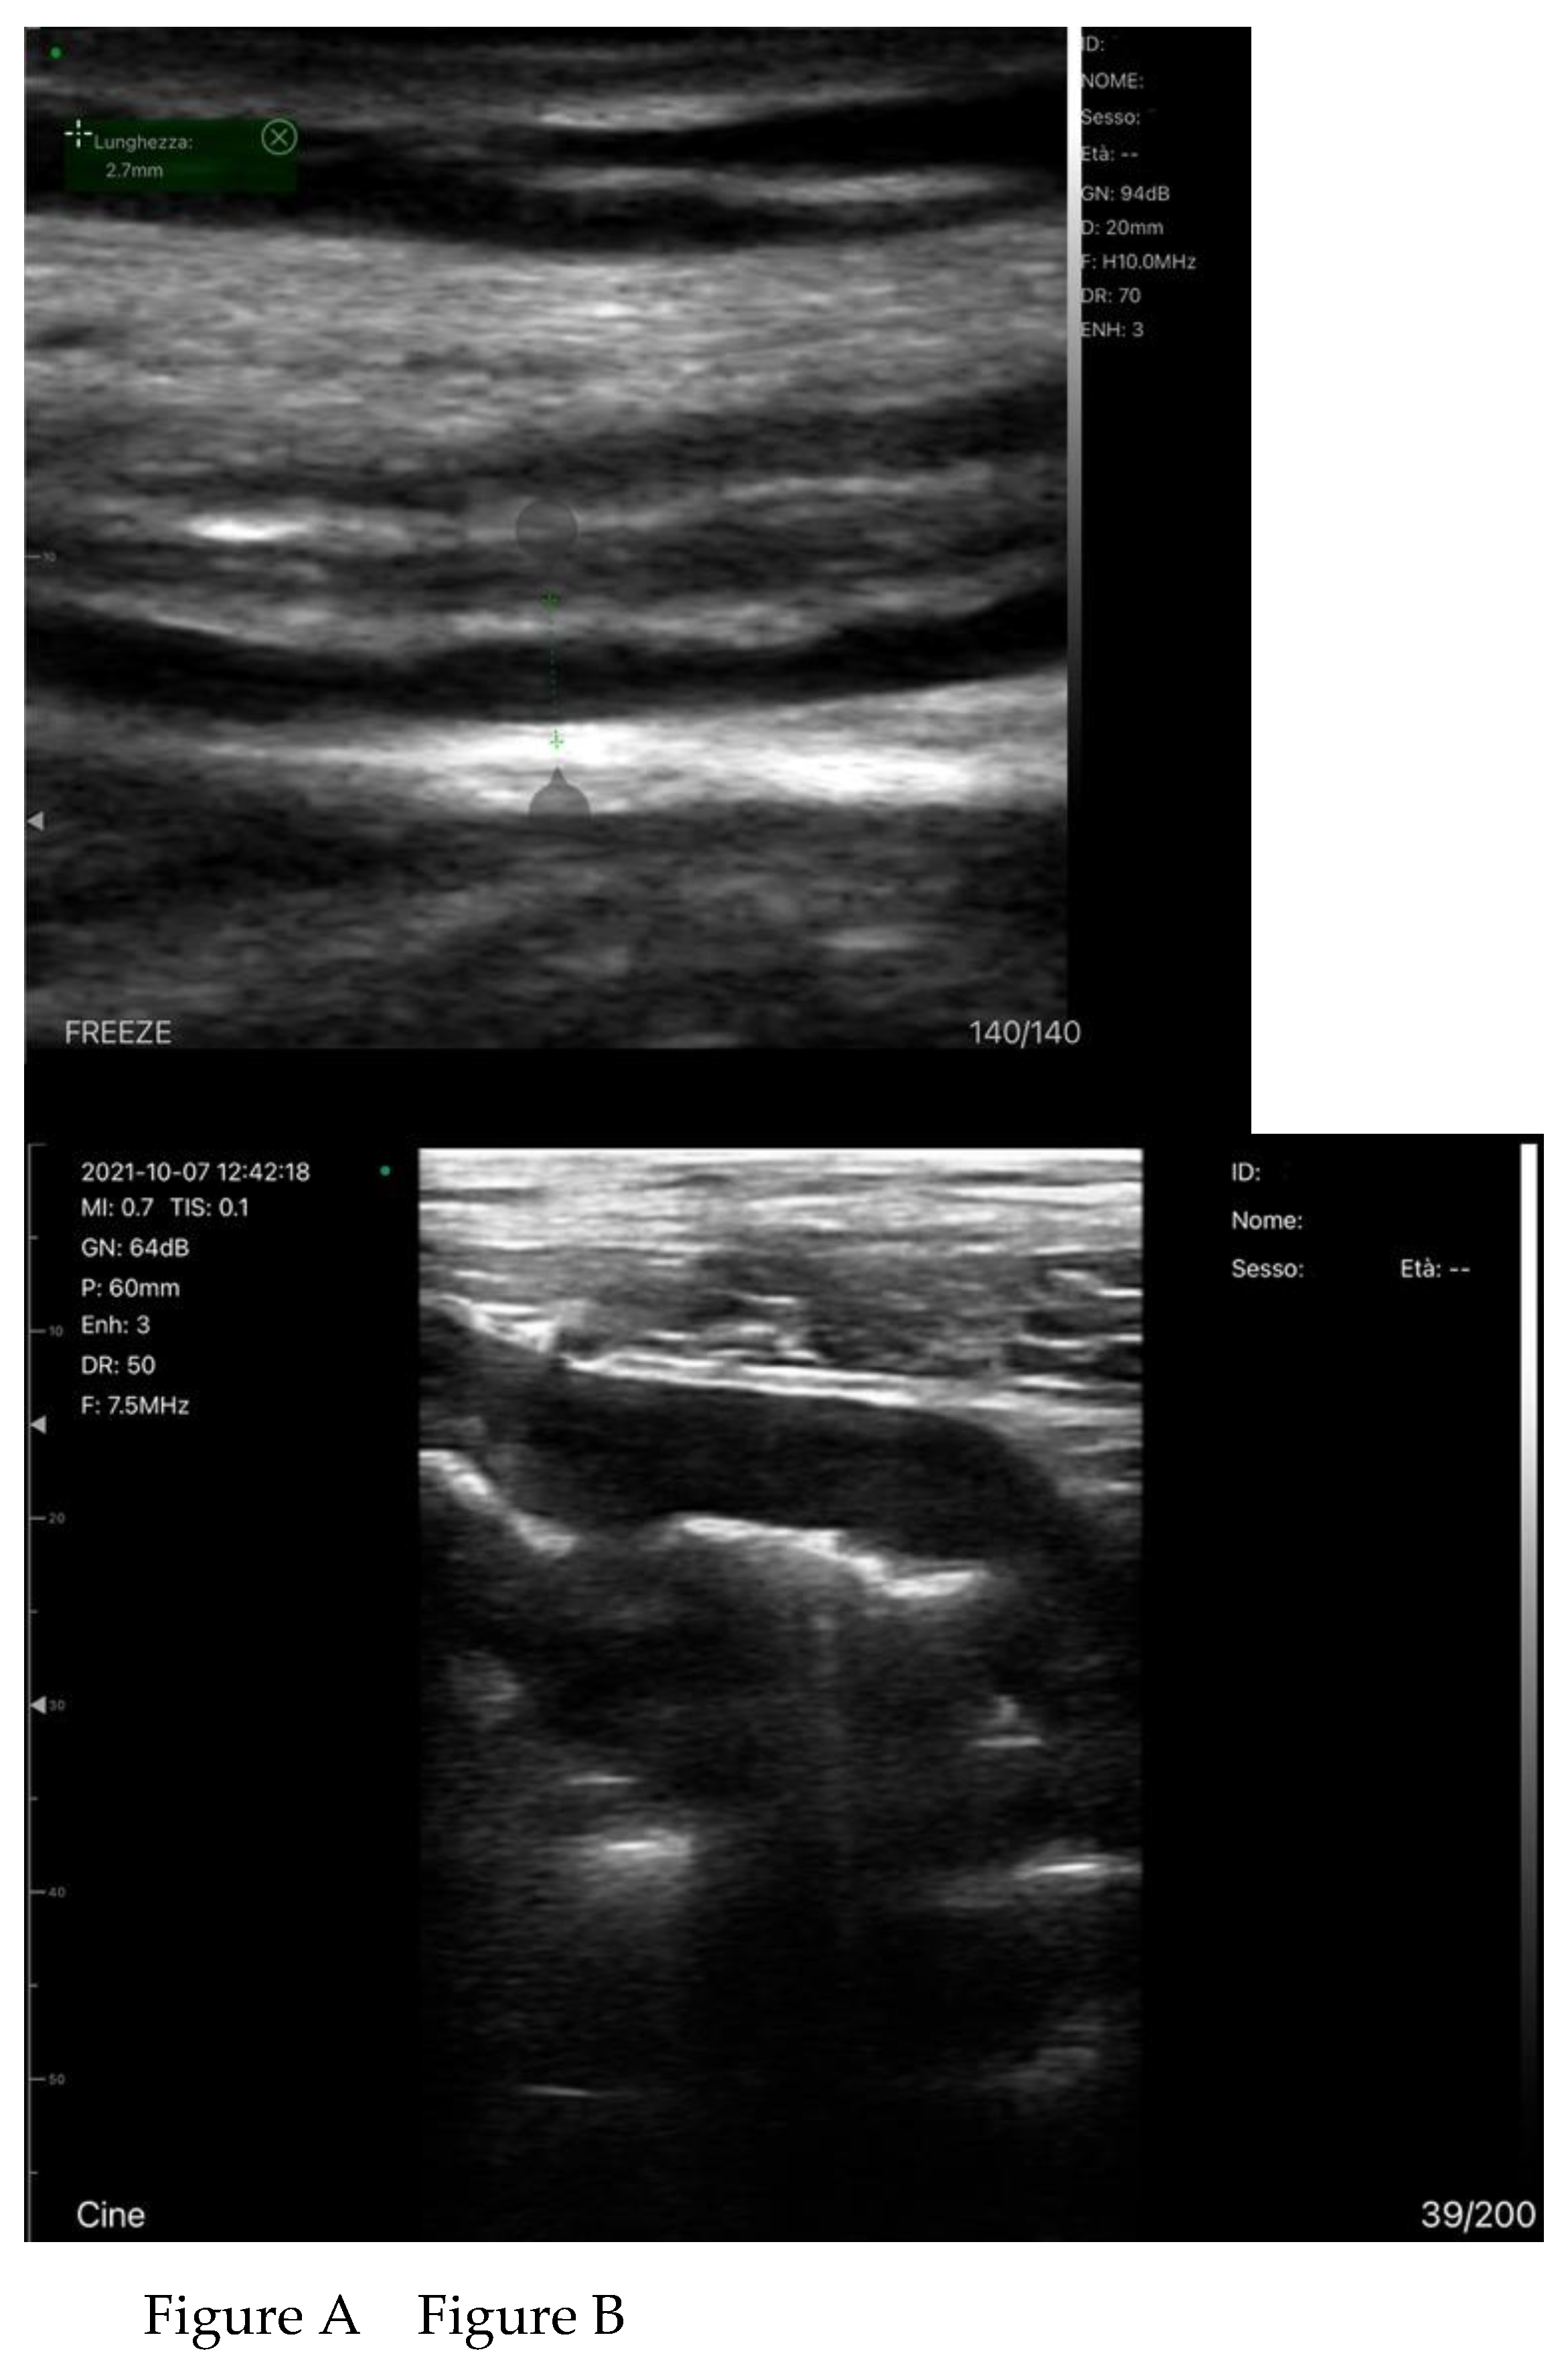

Bowel-Wall Thickening

Venous Congestion

- Ikeda, Y.; Ishii, S.; Fujita, T.; Iida, Y.; Kaida, T.; Nabeta, T.; Maekawa, E.; Yanagisawa, T.; Koitabashi, T.; Takeuchi, I.; et al. Prognostic impact of intestinal wall thickening in hospitalized patients with heart failure. International journal of cardiology 2017, 230, 120-126. [CrossRef]

- Ikeda, Y.; Ishii, S.; Maemura, K.; Oki, T.; Yazaki, M.; Fujita, T.; Nabeta, T.; Maekawa, E.; Koitabashi, T.; Ako, J. Association between intestinal oedema and oral loop diuretic resistance in hospitalized patients with acute heart failure. ESC Heart Fail 2021, 8, 4067-4076. [CrossRef]

- Hao, R.; Zheng, Y.; Zhao, Q.; Chen, J.; Fan, R.; Chen, P.; Yin, N.; Qin, H. Evaluation value of ultrasound on gastrointestinal function in patients with acute heart failure. Front Cardiovasc Med 2024, 11, 1475920. [CrossRef]